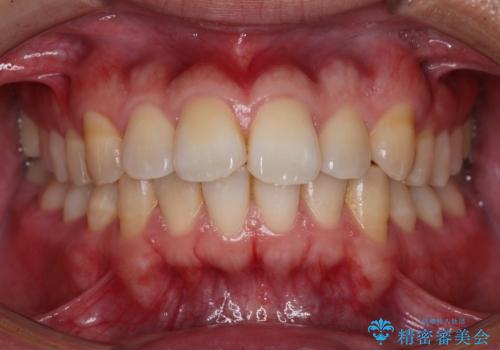

歯周ポケットの除去を併用したセラミック治療